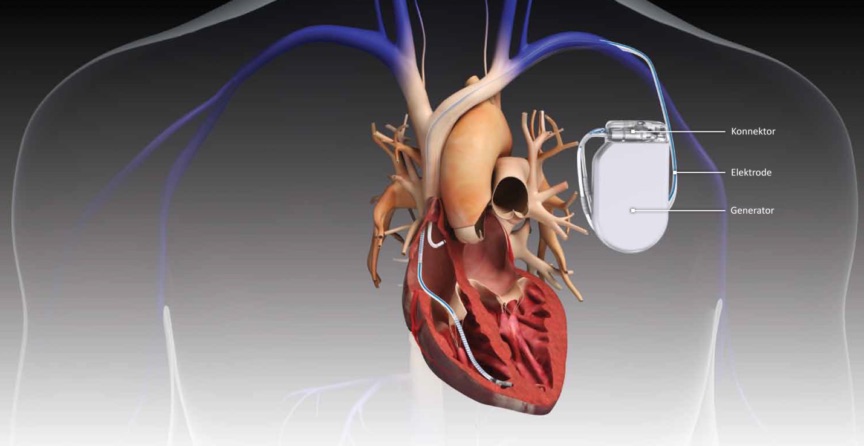

The Human Heart

There have been outstanding achievements in the treatment of heart failure. Technological advancements in heart treatment have reduced fatalities. An example is the artificial pacesetter placement that substitutes when the natural ones fail in order to improve a patient’s mortality. With every new technology, heart failure is becoming more manageable. As of 2018, about two million Americans suffered from severe heart failure each year. This is data collected before the development of the MitraClip, which is used to repair the mitral valve, which can significantly improve an individual’s quality of life.